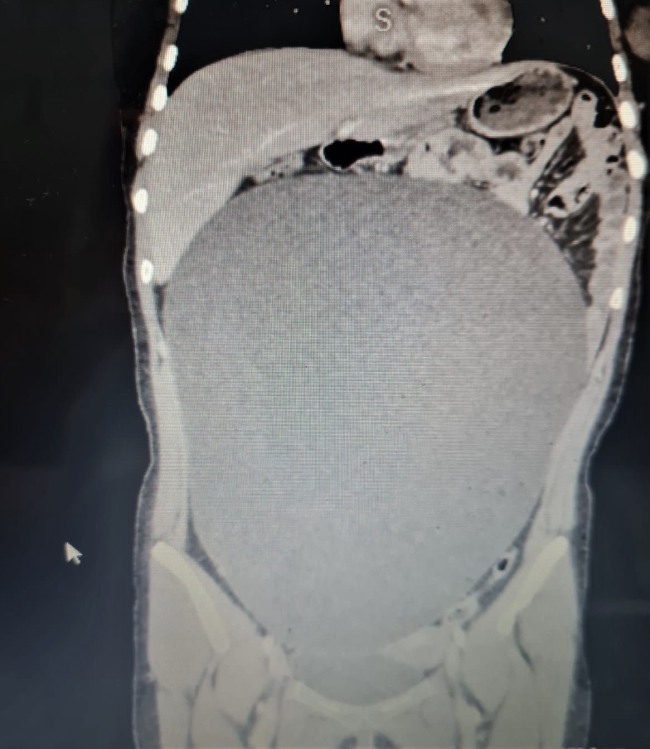

Burada yapılan tetkiklerde genç kızın karın bölgesinde anormal biçimde büyümüş bir kitle olduğu tespit edildi.

Hastanenin Çocuk Cerrahi Bölümü Uzmanı Dr. Öğretim Üyesi Ayşe Betül Öztürk tarafından acil şekilde ameliyat edilen B.G'nin karnından 60 santimetre çapına ulaşan yaklaşık 8 kilogramlık kitle başarıyla çıkarıldı.

Serviste hastanın tedavisine başladıklarını, tomografisinde karnında oldukça büyük bir kitle olduğunu gördüklerini anlatan Öztürk:

"Neredeyse bu kitle tüm karnını kaplıyordu. Aileyle görüşerek hızlı şekilde ameliyat kararı aldık. Ameliyat çok başarılı geçti. Sağ yumurtalık kaynaklı kitle başarılı şekilde alındı. Kitlenin organları sağa ve sola doğru sıkıştırdığını gördük. Kitle akciğer zarıyla temas halindeydi. Alt taraftan idrar torbasından akciğer zarına kadar uzanan oldukça büyük bir kitleydi. Bu kitle çok büyümüştü, eğer öğrenilmeseydi patlayabilirdi. Bu durumda da hayati tehlike ortaya çıkabilirdi. Daha da büyüyebilir ve ameliyat edilemez bir duruma gelebilirdi"